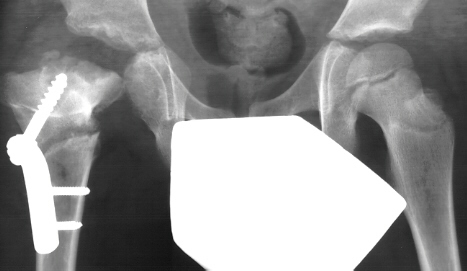

- 2 month Office Follow Up: Rt hip Xray: progressive destruction of capital

femoral epiphysis, cystic changes in metaphysis consistent with AVN.

- Age 6: Valgus osteotomy for subluxation and 2cm leg length inequality.

- Age 15: Valgus osteotomy for hip incongruity.

- Age 20: Hip arthroscopy. Hip fusion recommended.

This case is an example of untreated septic arthritis which caused avascular

necrosis of the proximal femur. The primary cause of this is undrained

septic hip. Repeated aspiration is not adequect treatment of a septic hip.